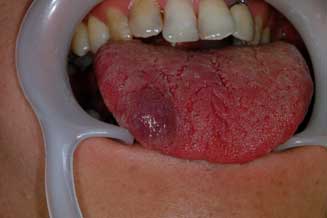

○ 非歯原性良性腫瘍:一般的な症状としては無痛性に周囲組織を圧排あるいは外向性に緩慢に増大

し、腫瘍が相当に大きくなるまでは機能障害もありません。腫瘍の種類として多いものは乳頭腫、

線維腫です。次に多いものは血管腫です。その他化骨性線維腫、リンパ管腫、脂肪腫などがありま

す。治療としては外科的切除が基本です。血管腫では薬剤を用いた硬化療法を行うこともあります。

| 舌線維腫 | 舌血管腫 | |